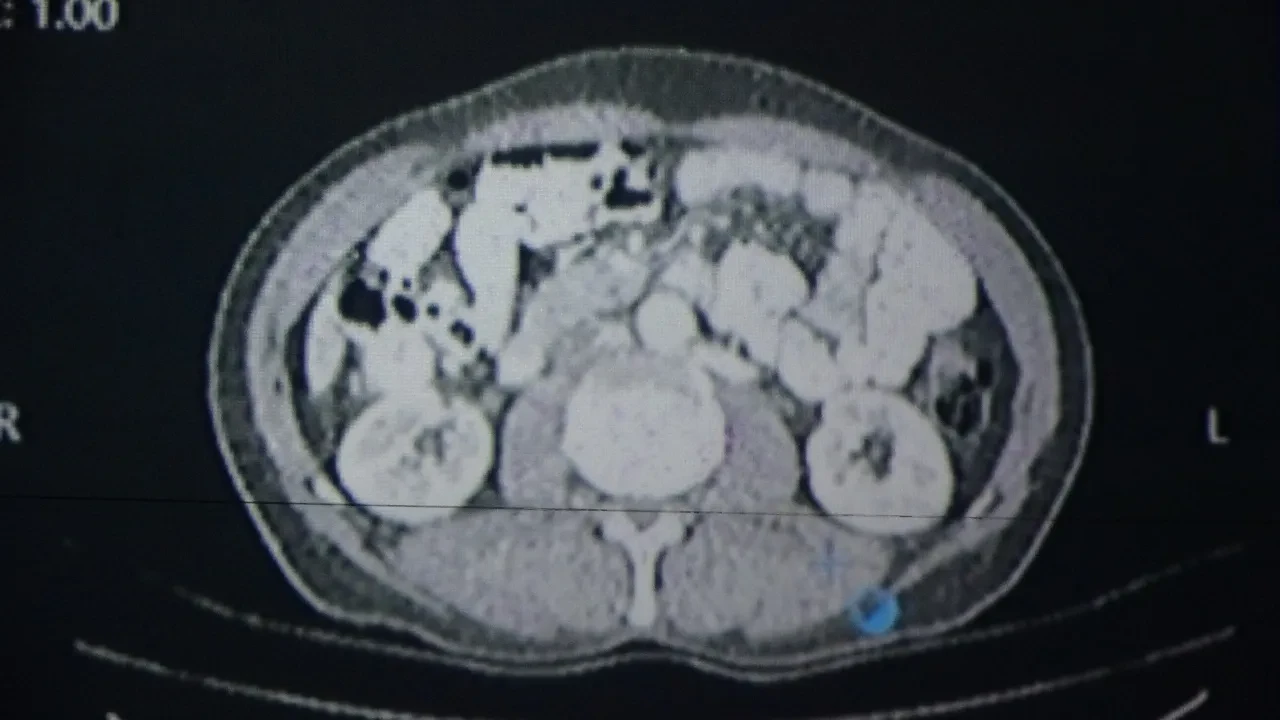

Prestijli uluslararası tıp dergisi Healthcare'de yayımlanan araştırmada; genel cerrahi, onkoloji, radyoloji, nükleer tıp, radyasyon onkolojisi ve patoloji uzmanlarının oluşturduğu konsey toplantılarına yapay zekâ destekli bir yazılım "katılımcı" olarak eklendi. Burada kanser tanısı konmuş 100 hasta hem hekimler hem de yapay zekâ tarafından değerlendirildi.

Kararların yüzde 76 oranında örtüşmesi, konunun bilimsel çevrelerde de dikkatle takip edilmesine neden oldu. Çalışmada örnek vakalardan biri olarak, Erciş ilçesinde yaşayan 56 yaşındaki Sabri Sarıyıldız değerlendirildi. Yapay zekâ destekli yazılımın önerdiği tedavi planı, hekimlerin kararlarıyla birlikte uygulamaya konuldu. Sarıyıldız, izlenen bu yol sayesinde gerçekleştirilen başarılı cerrahi operasyon sonrası sağlığına kavuştu.

Konuya ilişkin konuşan Van Bölge Eğitim ve Araştırma Hastanesi Genel Cerrahi Uzmanı Prof. Dr. Sebahattin Çelik, yapay zekânın hekim kararlarıyla yüzde 76 oranında örtüştüğünü belirtti. Yapay zekânın sağlık alanında giderek daha yaygın kullanıldığı ifade eden Prof. Dr. Çelik, "Biz de Van Bölge Eğitim ve Araştırma Hastanesi olarak teknolojinin sunduğu en son imkânlardan faydalanarak hastalarımıza doğru tedaviyi ve doğru yaklaşımı sunmak için yapay zekâ algoritmalarını kullanıyoruz. Yakın zamanda prestijli bir dergide yayımlanan çalışmamızda, multidisipliner tümör konseylerinde yapay zekâ destekli bir yazılım kullandık. Bu konseylerde genel cerrahi, onkoloji, radyoloji, nükleer tıp, radyasyon onkolojisi ve patoloji gibi birçok farklı branştan uzman hekimler bir araya gelerek hastaların tedavi sürecine yönelik ortak kararlar almaktadır. Biz de bu konsey toplantılarında yapay zekâyı bir katılımcı olarak değerlendirdik. ChatGPT'nin son algoritmasını kullanarak kanser tanısı olan 100 hastamızı hem uzman hekimler hem de yapay zekâ değerlendirdi. Sonrasında alınan kararlar karşılaştırıldığında, yapay zekâ destekli verilen kararların hekimlerin kararlarıyla yaklaşık yüzde 76 oranında örtüştüğünü gördük. Bu oldukça çarpıcı ve önemli bir bulgudur. Çünkü bu durum, yapay zekâ algoritmalarının artık profesyonel bir meslek grubu olan doktorlara yakın düzeyde karar verebildiğini göstermektedir" dedi.